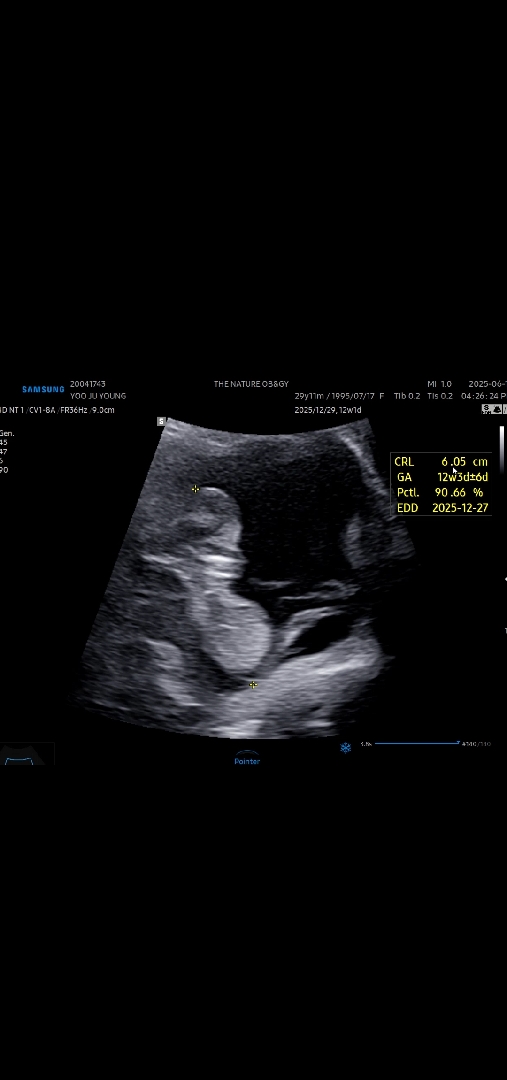

12주차 각도법좀 보려고 했더니.. ㅋㅋ

누워있지 않고 제가 소파에 기대서 티비볼때처럼 자궁을 쿠션삼아 앉아있는데 ㅋㅌㅌㅌ 양수 넉넉하고 자궁도 좁진 않다 햇는데 12주촘파때 이렇게 앉아있던 아기 있나요? ㅋㅋㅋㅋ